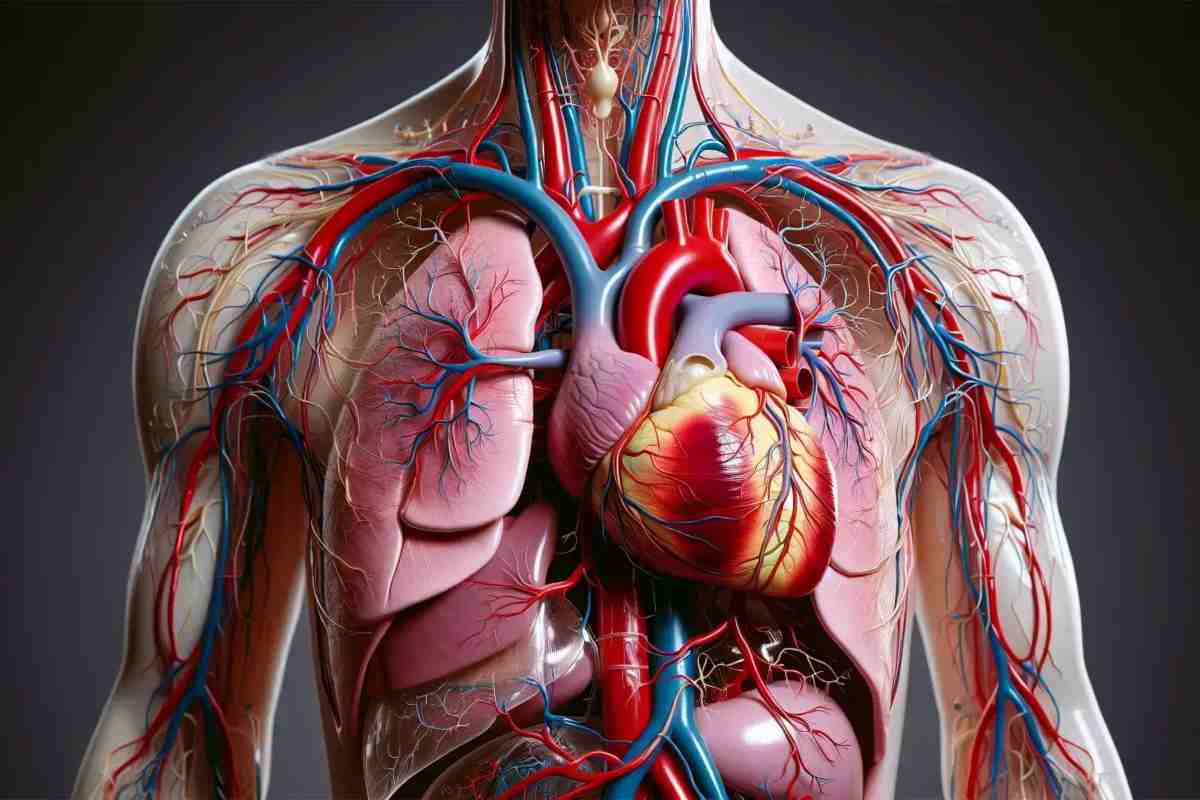

Gli esperti si sono serviti di una tecnica a raggi X per ottenere preziose informazioni da un cuore sano e da un cuore malato di due persone decedute. Questo vero e proprio atlante 3D riguarda sia l’intero organo del nostro corpo che le singole cellule, i vasi sanguigni e le valvole.

La tecnica a raggi X usata dai ricercatori consente di mostrare le singole cellule dell’organo. Si sono ottenute delle perfette immagini in 3D complete e dettagliate nei minimi particolari. Esse sono incentrate sull’assorbimento e sulla rifrazione dei raggi X da parte dei tessuti.